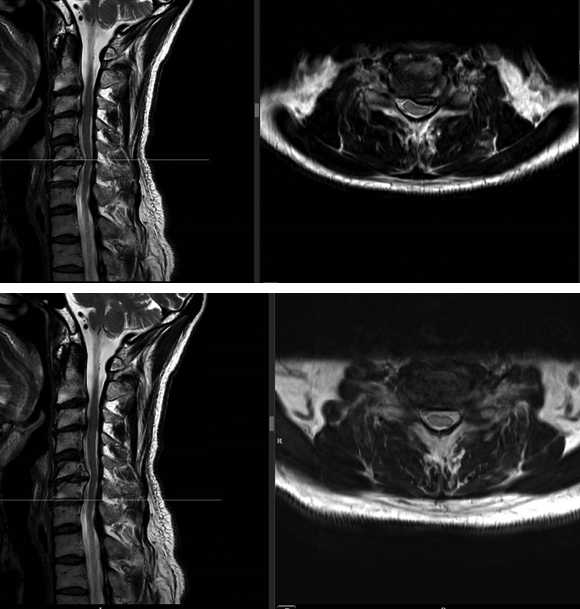

A magnetic resonance imaging demonstrated a cervical spinal stenosis with cord compression C5-6 L, foraminal stenosis C5-6 L, and C6-7 bilateral (Fig 5).